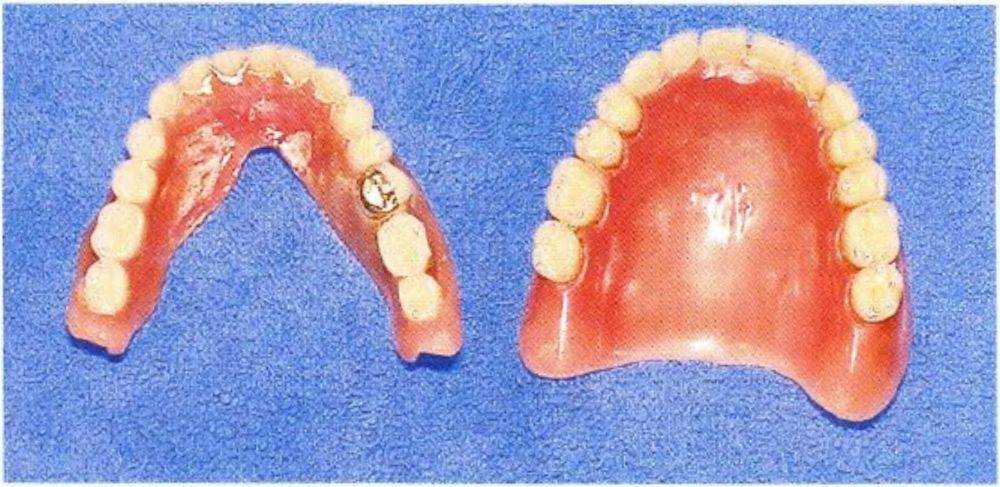

При осмотре определили выраженную атрофию альвеолярных гребней верхней и нижней челюсти, а также сниженную саливацию. Съемные протезы были несостоятельны (рис. 1 -9с). В связи с анамнезом и данными осмотра возникло несколько вопросов:.

Рис. 1-9с. Плохоприпасованная пара съемных полных протезов